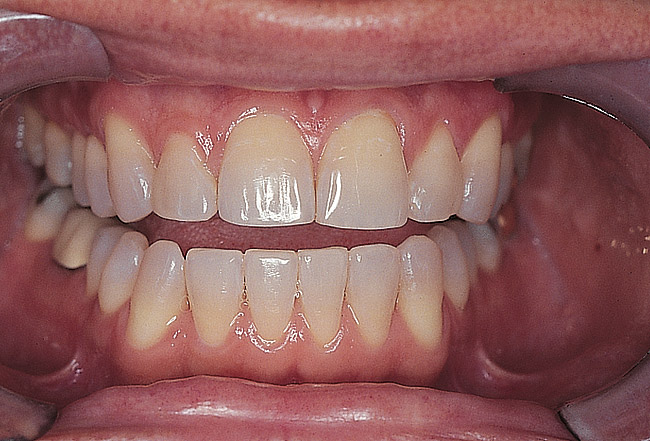

Figure 3  Preoperative intraoral facial view.

Figure 3

Figure 8  Facial view following 7 months of orthodontic treatment.

Figure 8

Figure 9  Immediate post-orthodontic facial view.

Figure 9